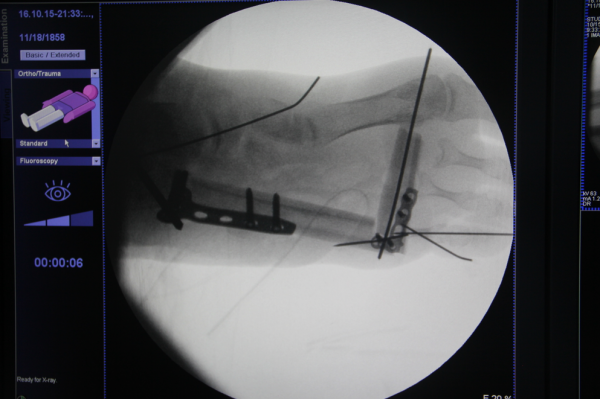

昨天急诊小皮瓣

QQ截图20160919232401.png QQ截图20160919232425.png QQ截图20160919232442.png QQ截图20160919232457.png